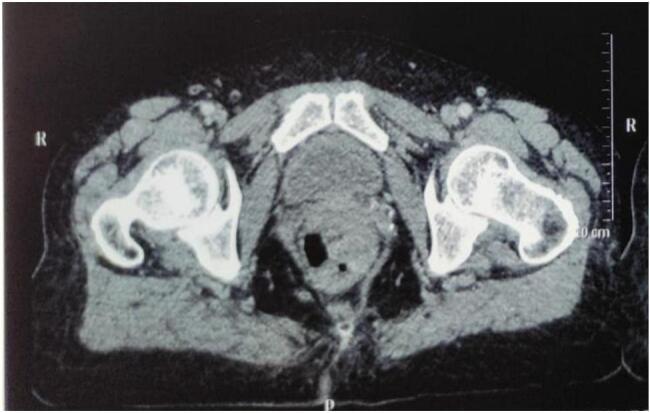

In this study, we report two cases of patients who experienced different anorectal symptoms for a long time before their condition worsened, prompting further investigation that revealed a diagnosis of malignant anorectal melanoma. Both patients underwent surgical resection and are currently receiving adjuvant therapy.

Anorectal melanoma is a rare pathology, and its prognosis is poor due to the frequent presence of metastatic forms at the time of diagnosis. Surgery, whether through abdominoperineal amputation or wide local excision, is the treatment of choice for these tumors. The use of radiotherapy (RT) is controversial and is currently indicated either as hypofractionated therapy following local excision (EL) or as palliative treatment.